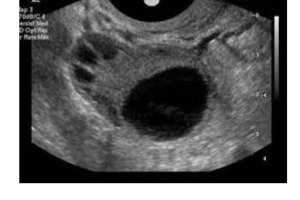

卵泡监测

卵泡监测有什么用 卵泡监测是针对女性不孕的一种检查方法,能够通过卵泡检查发现女性不孕的病因,在试管婴儿手术中,卵泡监测技术也被普遍运用,期作用如下: 1、根据卵泡监测报告分析女性是卵泡发育问题还是排卵障碍问题; 2、试管婴儿中卵泡监测的用处主要是为了观察卵泡发育情况,以确定是否促排成功,制定取卵时间…